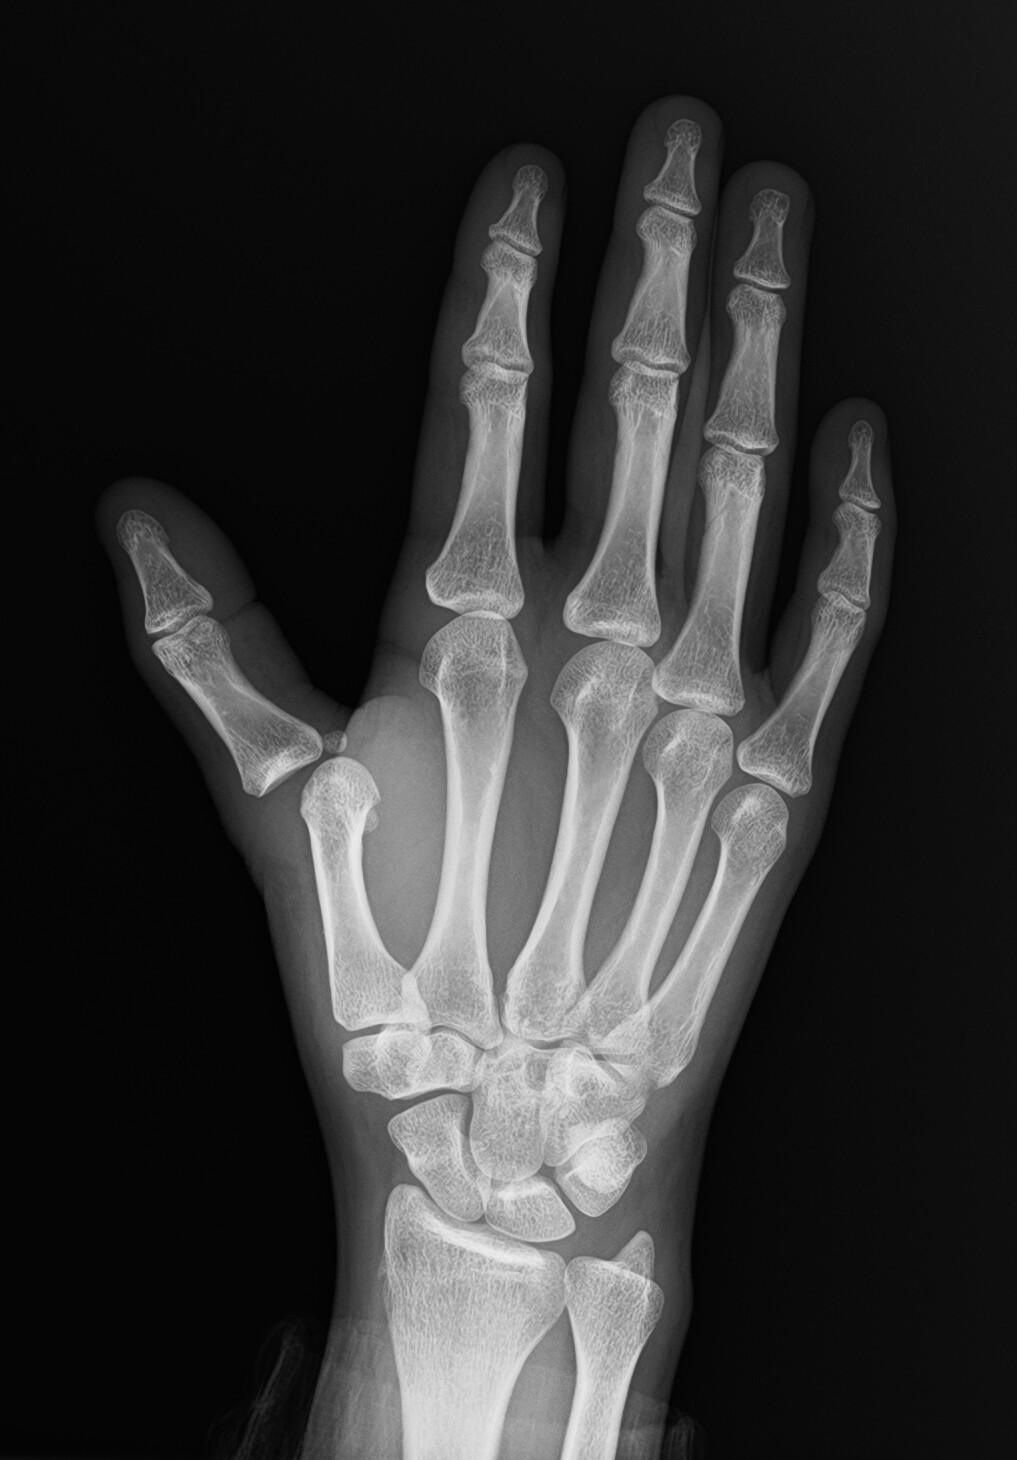

Luxation MCP du pouce

Radiopaedia.org

. From the case

rID: 160809

Avis chirurgical

systématique.

Demander une

radiographie F+P strict.